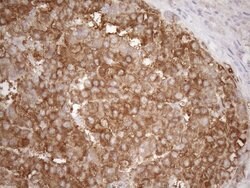

| Immunohistochemistry (Paraffin), Western Blot | |